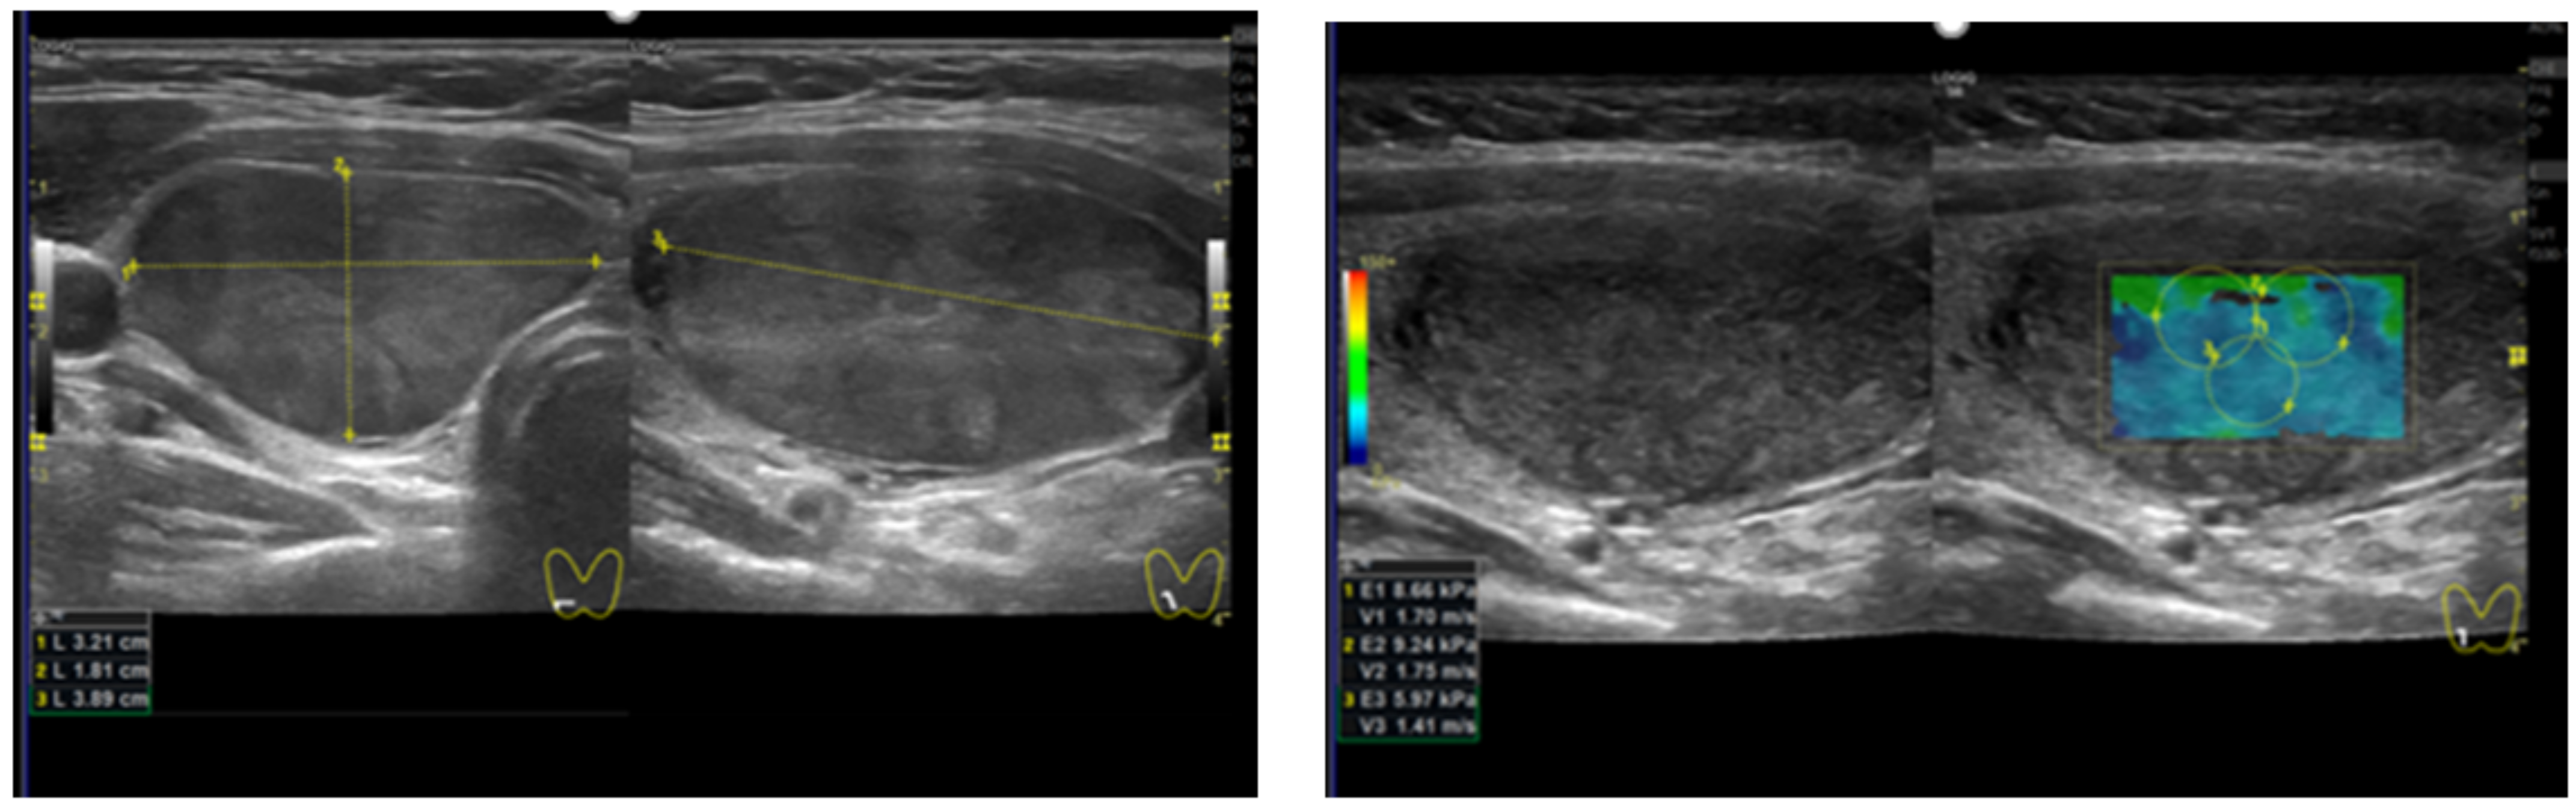

2.2. Thyroid US and SWE